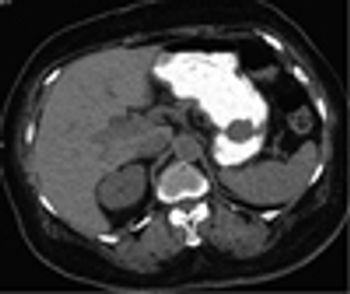

Carney’s TriadByValerie D'Aurora, MD,Michael Sadler, MDFebruary 12th 2013A 77-year-old woman presented to the emergency department complaining of diarrhea for five days and abdominal pain.